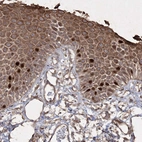

Immunohistochemistry analysis in human testis and pancreas tissues using HPA034521 antibody. Corresponding PRC1 RNA-seq data are presented for the same tissues.